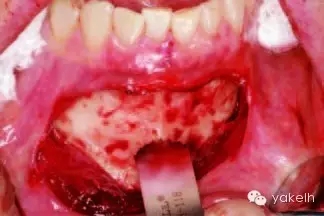

¤¤暴露頦部后,設(shè)計取骨的切口。取骨塊的大小由受區(qū)所需的骨量決定。骨切開處距離根尖以及頦孔最少應(yīng)有5mm。多數(shù)情況下,要保留下頜骨下緣以及舌側(cè)皮質(zhì)骨的完整性。唇側(cè)皮質(zhì)較厚,其內(nèi)側(cè)的松質(zhì)骨通常較致密??梢允褂脺u輪手機(jī)碳合金裂鉆(557號或701號)或者來復(fù)鋸將骨切開(圖13.19)。切透皮質(zhì)骨達(dá)松質(zhì)骨后,用骨鑿將骨塊移除(圖13.20)。用單面鑿沿著骨切開線輕輕敲擊,除了下頜骨下緣,將骨塊從基底部折斷。在中線處時,也可將塊狀骨分割成矩形骨塊,分段獲取。分成兩個骨塊后更容易獲取,因為可以用骨鑿將第二塊骨塊從舌側(cè)撬起。另外,移除塊狀骨后,還可使用骨刮匙、鑿子、咬骨鉗、環(huán)形鉆獲取

一些松質(zhì)骨,但是松質(zhì)骨的量十分有限。在移除塊狀骨后,可以將止血材料如膠原或明膠海綿置于松質(zhì)骨表面。當(dāng)獲取較大的骨塊時,供區(qū)應(yīng)使用骨替代材料如羥基磷灰石,來維持唇側(cè)的外形(圖13.21)。較少或者顆粒狀的骨移植時,可使用環(huán)形鉆、骨收集器、骨挖器來獲取。把骨塊植入受區(qū)后,再將供區(qū)的傷口縫合,這可以縮短取骨與植骨之間的時間。分離前庭溝切口上方的黏膜,以減少水腫和下唇運動所產(chǎn)生的張力。用可吸收縫線分層縫合前庭溝切口(圖13.22)。深層組織使用4-0可吸收線縫合,表層黏膜使用4-0鈷腸線縫合。術(shù)后使用壓力繃帶包扎頦部,以減少水腫、血腫形成及切口裂開(圖13.23)。